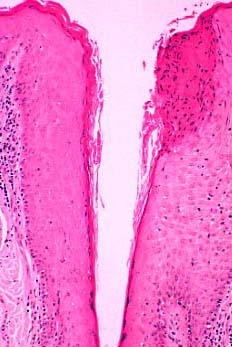

Histopathology. The histopathologic features are a combination of those observed in psoriasis and spongiotic dermatitis. Mild cases may exhibit only slight subacute spongiotic dermatitis. The stratum corneum contains focal parakeratosis, with a predilection for the follicular ostia, a finding known as shoulder parakeratosis . Occasional pyknotic neutrophils are present within parakeratotic foci {neutrophilic parakeratosis}, sometimes with fluid {neutrophilic crust}. There is moderate acanthosis with regular elongation of the rete ridges, mild spongiosis, and focal exocytosis of lymphocytes. The dermis contains a sparse mononuclear cell infiltrate. In HIV-infected patients, the epidermis contains apoptotic keratinocytes, and the dermal infiltrate usually contains plasma cells. |